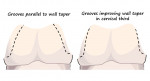

For preparations that are somewhat short or over-tapered, auxiliary retentive features such as axial grooves or boxes, preferably on proximal surfaces, may be considered to enhance the geometry for retention and resistance and permit conventional cementation of the crown (Figure 5).5 One early study reported that the use of interproximal grooves and boxes increased the resistance form of tooth preparations. It also reported that the placement of boxes was more effective than the placement of grooves.8 In another study, the authors reported that grooves and boxes were not effective at increasing resistance form for an over-tapered preparation with greater than 20° total occlusal convergence.9 However, they did indicate that grooves would be expected to be effective if they were prepared with less taper in the cervical third of the tooth to improve the overall taper of the preparation (Figure 6).